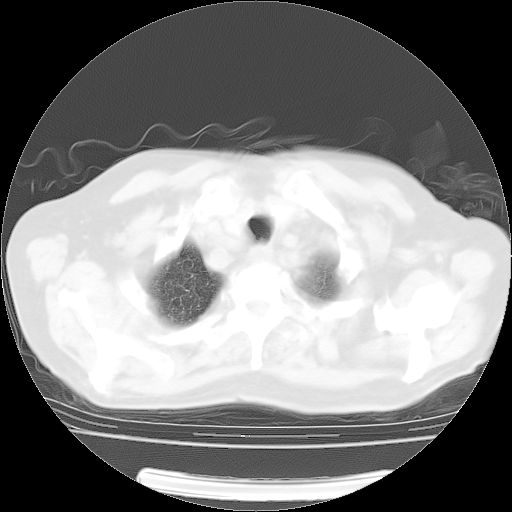

4月28日肺部CT——再次出现类似去年5月9日——透光度降低,(影像科认为)“间质性”改变。

1221483 1 .bmp

1221483 2 .bmp

1221483 3 .bmp

1221483 4 .bmp

1221483 5 .bmp